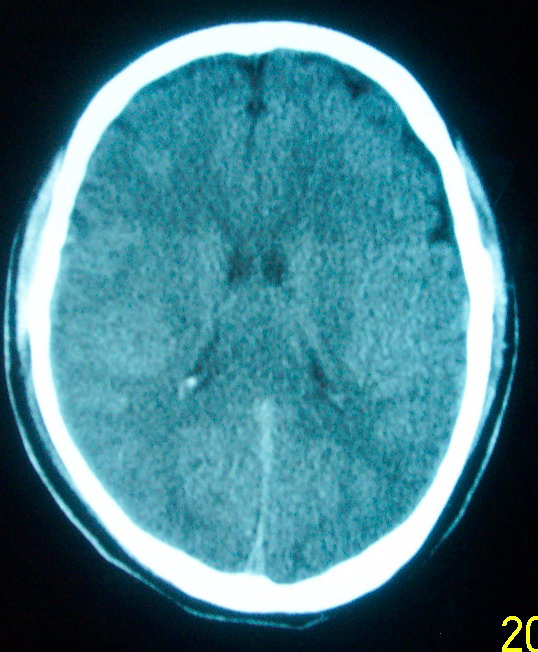

m     29    外伤1天   ct发现左额脑沟异常   请分析

我认为仅仅是左侧额叶脑回局部发育不良,脑沟与蛛网膜下腔略扩大而已没有巨脑回、硬膜下积液等情况。